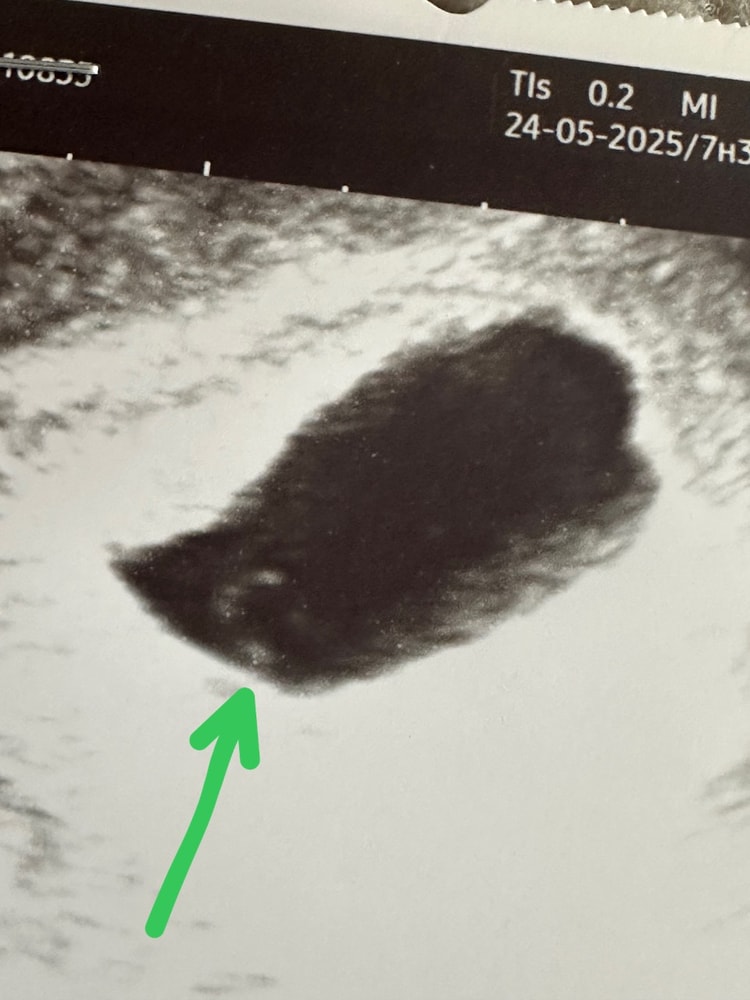

Решаю вечером посетить свою ЖК, мол вот 17.07 должна к вам на учет вставать, но тут такое дело, мне некуда идти сейчас, и я не знаю что делать. Меня отправляют к дежурному врачу и я просто влюбляюсь в нее, если бы она еще на моем участке бы работала, я бы летала к ней 🥰 Она слушает историю и говорит, что это бывает так, клинику хорошую я мол выбрала, и тут я показываю ей узи, она видит ЖМ и говорит, а давайте подождём? У вас появился ЖМ, ничего не мешает сейчас просто подождать, неделю всего. Завтра езжайте, смотрите по узи, и если есть динамика, давайте попробуем вести беременность. У меня шок, опять надежда, напомню, у меня капризный эндометрий и мне нельзя ни вакуум, ни выскабливание, это для меня вообще конец.

Смотрит…считает…3 дня прошло, и показывает мне моего эмбриончика, маленькую «рисенку» размером КТР - 1,3 мм. Говорит, беременность желанная - надо ждать, неделю! Сердце нет возможности посмотреть, так как еще очень мал он. ЖТ хорошее, отслоек нет. Одеваюсь и выхожу. Врач остается писать заключение.